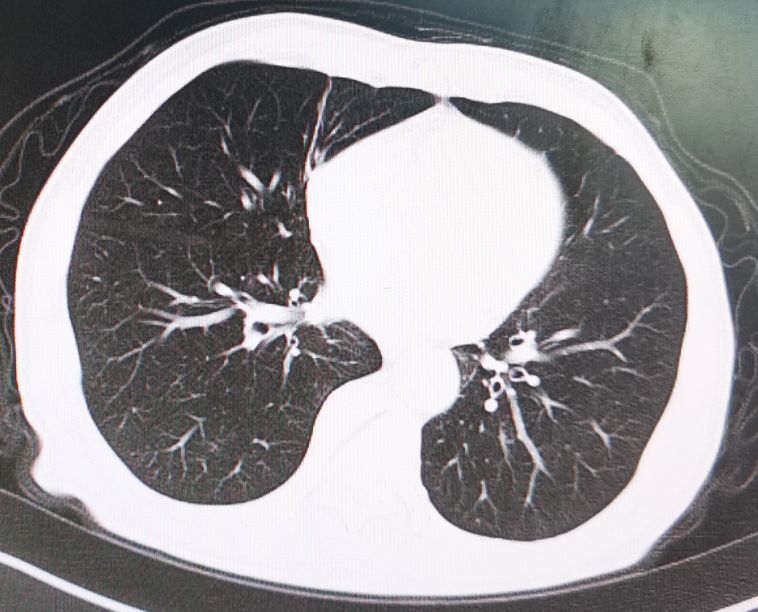

术后一年半的时候,常规复查时发现病人双肺出现明确的转移病灶,但患者一般情况及营养状况比术前有所好转,随后给予联合化疗和靶向药物治疗。

肺部CT显示左右肺均有转移病灶

经联合化疗及靶向药物治疗六个周期后,病人双肺的转移病灶完全消失,随后进行维持治疗至今没有发现新的转移病灶。

6个周期化疗及靶向药物治疗后转移病灶完全消失